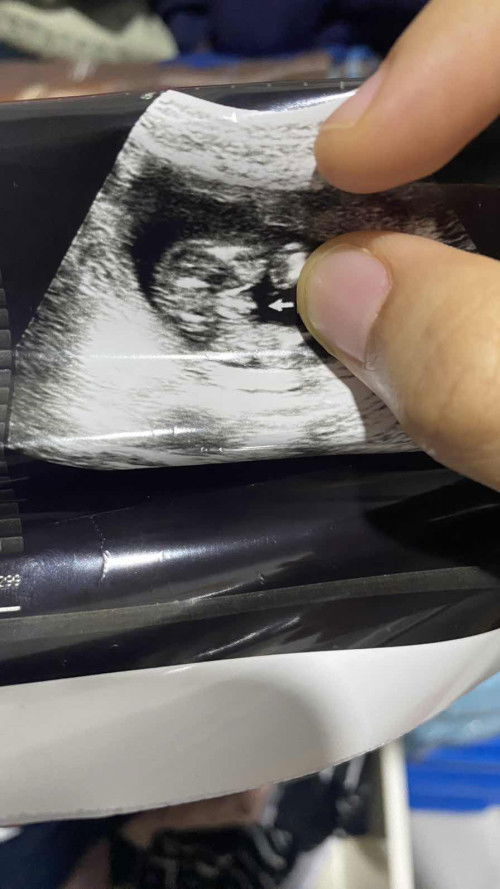

Boy ke girl? Pinjam mata korang jap scan 19 weeks

Boy ke girl? Conpius😂

Doctor/sono takde bagitahu ke awak? Kalau tak yakin, boleh repeat scan lagi 😊

macam boy sis

mcm boy..hehe

Mcm boyyy

lalaki